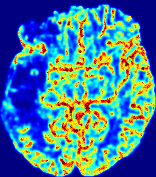

4.3.1 Advection Imaging via Advection-Diffusion

Slice #1Slice #2Slice #3Slice #4Slice #5Slice #6𝐕gt𝟐subscriptnormsuperscript𝐕gt2\|\bf{V}^{\text{gt}}\|_{2}Refer to captionRefer to captionRefer to captionRefer to captionRefer to captionRefer to caption𝐕est𝟐subscriptnormsuperscript𝐕est2\|\bf{V}^{\text{est}}\|_{2}Refer to captionRefer to captionRefer to captionRefer to captionRefer to captionRefer to captionRefer to caption1.51.51.51.21.21.20.90.90.90.60.60.60.30.30.30.00.00.0(mm/s)𝑚𝑚𝑠(mm/s)Destsuperscript𝐷estD^{\text{est}}Refer to captionRefer to captionRefer to captionRefer to captionRefer to captionRefer to captionRefer to caption0.0150.0150.0150.0120.0120.0120.0090.0090.0090.0060.0060.0060.0030.0030.0030.0000.0000.000(mm2/s)𝑚superscript𝑚2𝑠(mm^{2}/s)

Figure 14: PIANO identifiability testing: advection imaging via advection-diffusion. Top row shows 𝐕gt2subscriptnormsuperscript𝐕gt2\|{\bf{V}}^{\text{gt}}\|_{2} used for simulating ground truth pure advection. Rows below show the estimated 𝐕est2subscriptnormsuperscript𝐕est2\|{\bf{V}}^{\text{est}}\|_{2} and Destsuperscript𝐷estD^{\text{est}} on corresponding slices. Note that the plotted value scale for Destsuperscript𝐷estD^{\text{est}} is 0.01 of that for 𝐕gt2subscriptnormsuperscript𝐕gt2\|{\bf{V}}^{\text{gt}}\|_{2} and 𝐕est2subscriptnormsuperscript𝐕est2\|{\bf{V}}^{\text{est}}\|_{2}.

We use the same ‘Advection Imaging’ simulation of Sec. 4.2.1 as the concentration dataset for PIANO. However, instead of modeling pure advection (Eq. 15), we let PIANO estimate both velocity 𝐕estsuperscript𝐕est{\bf{V}}^{\text{est}} and diffusivity Destsuperscript𝐷estD^{\text{est}} via the advection-diffusion PDE (Eq. 2) underlying the proposed PIANO model. Fig. 14 shows the estimated 𝐕est2,subscriptnormsuperscript𝐕est2\|{\bf{V}}^{\text{est}}\|_{2}, and Destsuperscript𝐷estD^{\text{est}} fields for one patient. Although PIANO has the freedom to estimate both a velocity and a diffusivity field from pure advection, PIANO differentiates well between advection and diffusion: the estimated 𝐕est2subscriptnormsuperscript𝐕est2\|{\bf{V}}^{\text{est}}\|_{2} successfully reproduces the ground truth 𝐕gt2subscriptnormsuperscript𝐕gt2\|{\bf{V}}^{\text{gt}}\|_{2} governing the simulated advection process, just as it already did in the ‘Advection Imaging via Advection’ test (Fig. 12). More importantly, the estimated diffusivity Destsuperscript𝐷estD^{\text{est}} is orders of magnitudes smaller than 𝐕est2subscriptnormsuperscript𝐕est2\|{\bf{V}}^{\text{est}}\|_{2}, indicating the estimated diffusion is negligible compared to the estimated advection, which is highly consistent with the underlying pure advection of the simulated data.